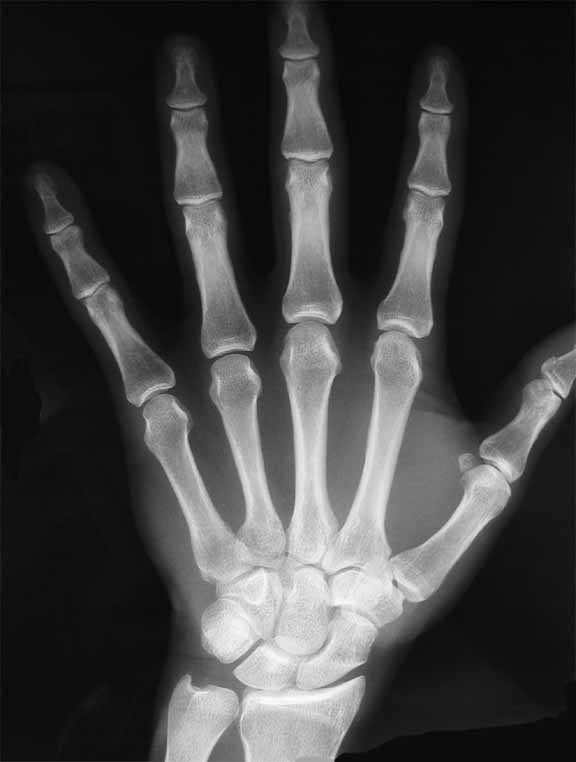

Рис. 4. Современная рентгенограмма кисти руки. Изображение с сайта www.articlesweb.org